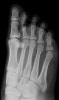

새끼 발가락의 원위지골과 중지골이 선천적으로 유합되어 있는 사람이 적지 않습니다.

제4족지, 나아가 제3족지까지 DIP 관절이 유합되어 있는 경우도 있습니다.

소지에서는 PIP 관절도 유합되어 하나의 지골이 될 수도 있지만 드뭅니다.

X-ray : 선천성 지절유합증(Congenital symphalangism)